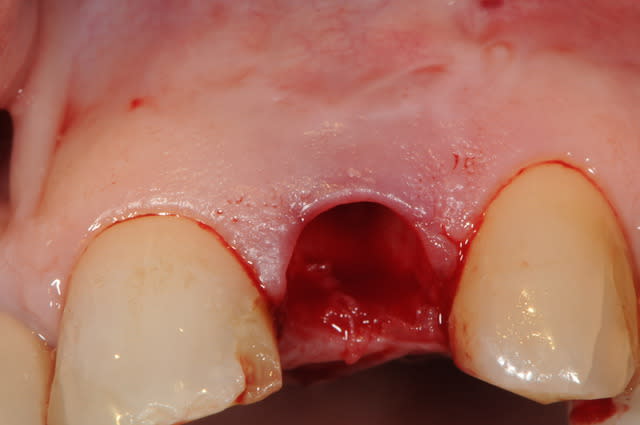

Le cas EII sur 12

positionnement de l'implant en ménageant un espace en vestibulaire qui st comblé avec de l'os synthétique car l'espace est important et il y a une perforation de la corticale vestibulaire en regard de l'apex de la dent.

pour recouvrir tout cela et gagner un peu de volume vestibulaire

un lambeau palatin pédiculé qui après une rotation va recouvrir l'implant et la greffe.